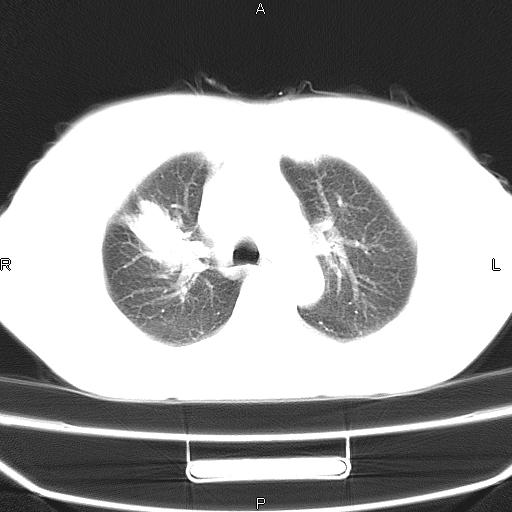

患者,女,66岁。健康体检胸部透视发现右上肺片状阴影。既往无不适,患者自诉三个月前曾有低热病史体温37.5左右一周。用药后缓解。至今无其它不适。请老师们指导指导。

考虑:右肺上叶周围型肺癌(分叶状肿块+砂粒状钙化+胸膜尾征)。

病灶见明显分叶、大小较大(大于3cm?),老年人,多考虑:肺癌,建议穿刺活检。

典型的中心型肺癌,尖段支气管阻塞。

周围性肺癌,

周围性肺癌

右肺上叶周围型肺癌可能性大。

考虑:右肺上叶周围型肺癌